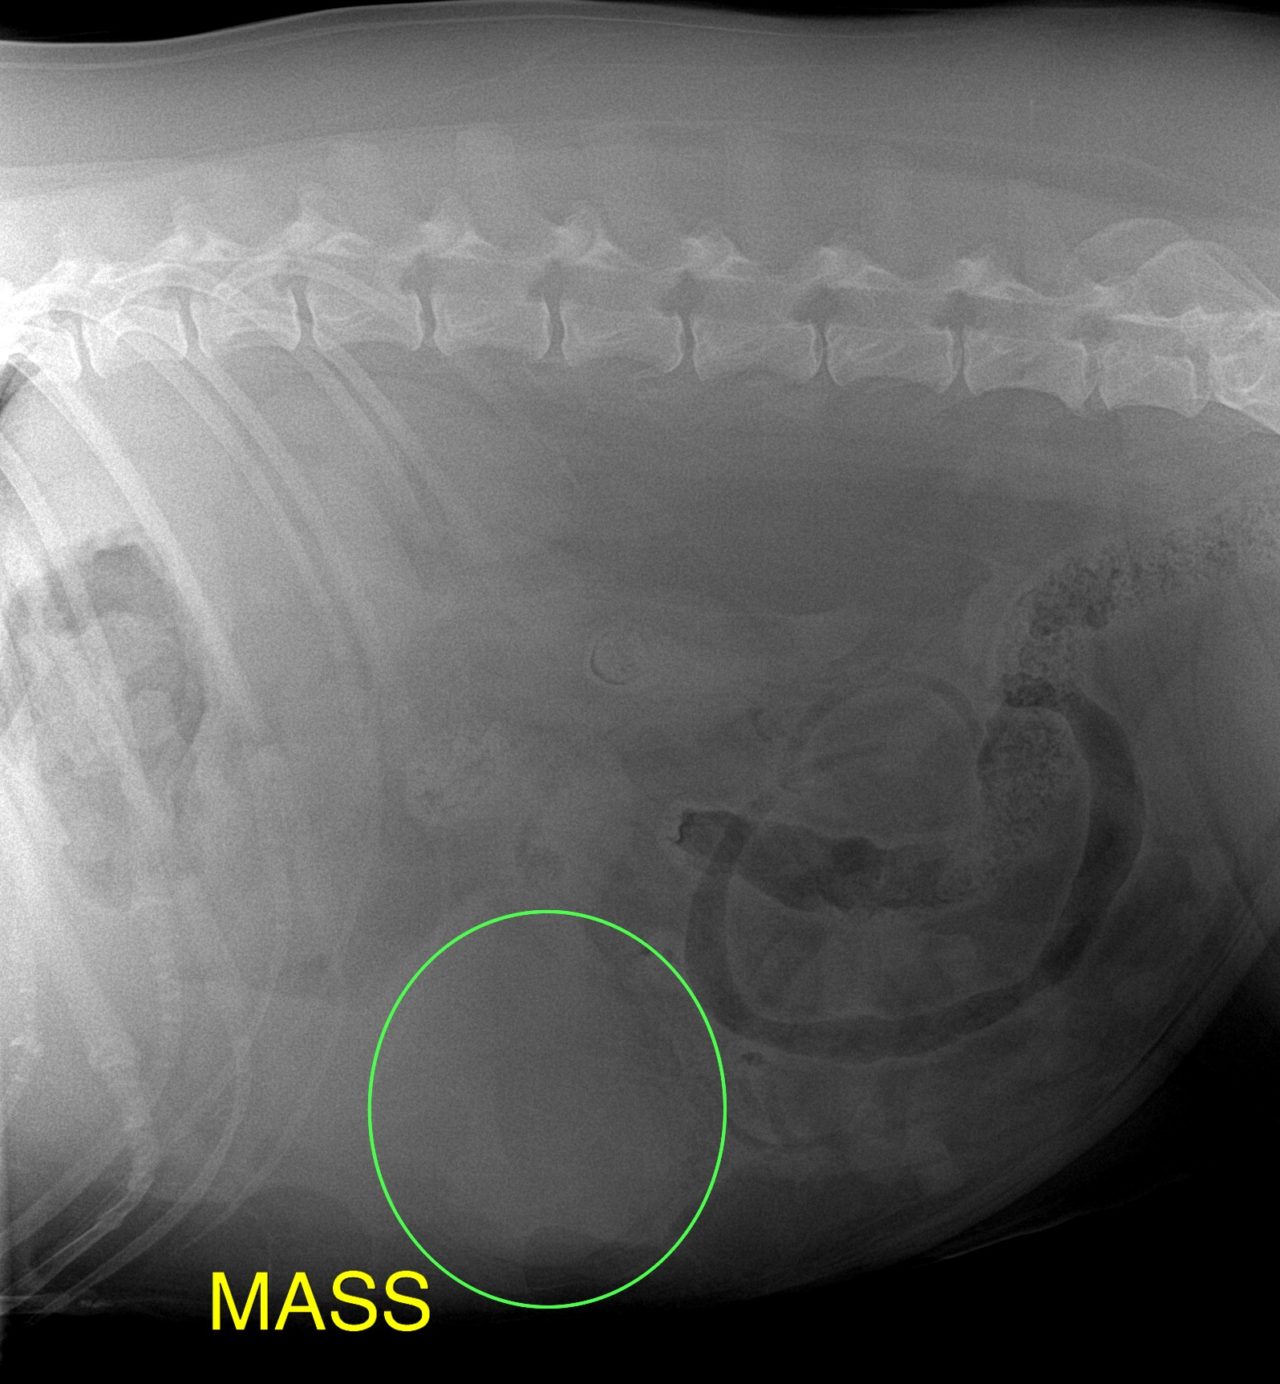

歯茎白い。すぐさま腹部の超音波検査をして”腹腔内液体貯留と腹腔内腫瘤を確認”

エコーでは脾臓と肝臓にMASSを確認。

開腹すると脾臓と肝臓に腫瘤病変があり破裂、出血していました。